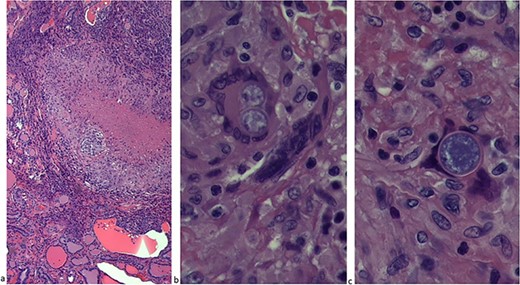

The patient underwent an uncomplicated thyroidectomy. Histopathologic examination demonstrated a thyroid (108 grams) with nodular and hyperplastic thyroid follicles. Several small nodules in the right lobe consisted of caseating and noncaseating granulomas (Fig. 3a) with spherules (10–40 μm) characteristic of Coccidioides immitis (Fig. 3b and c). No neoplasm was present in any of the tissue. Pathology was negative for acid-fast stain for Mycobacterium. Subsequent CT of the chest showed extensive bilateral miliary nodules. The patient was started on oral fluconazole therapy at 400 mg/d.

(a) The thyroid lobe consisted of caseating and noncaseating granulomas. (b) Thyroid lobe with spherules (10–40 μm). (c) C. immitis.